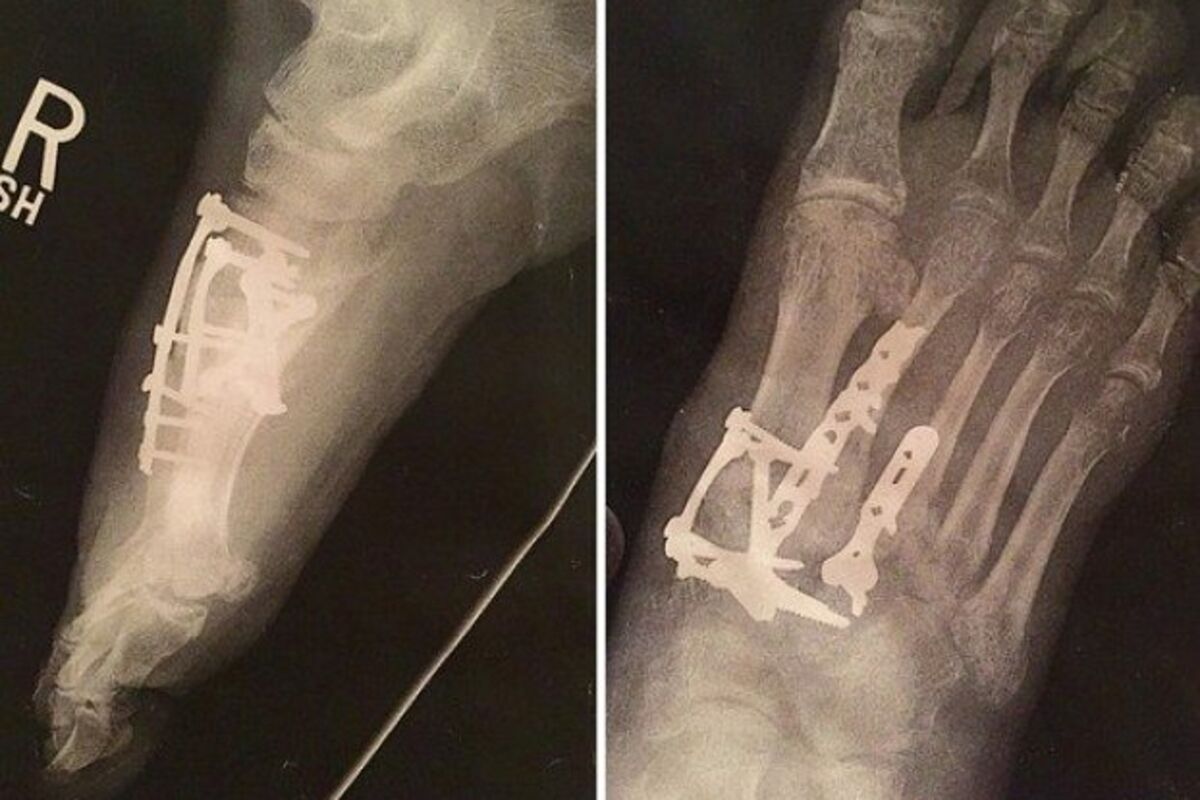

Evo o kolikom se šrafu radilo: